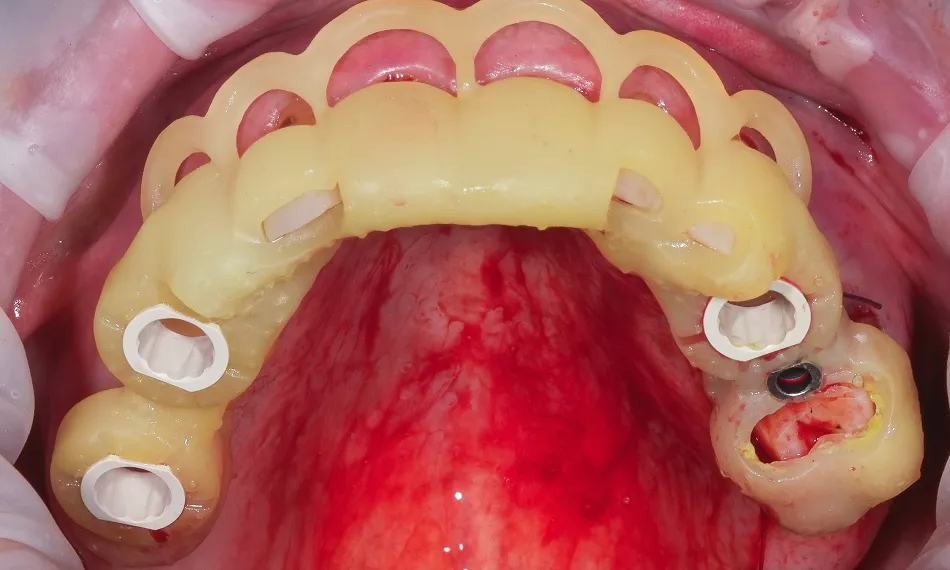

Early loading was applied to the four maxillary implants, while immediate loading was performed for the four mandibular implants. The provisional restoration was delivered the day after surgery using screw-retained abutments (SRA), torqued to 35 Ncm, and a screw-retained prosthesis that was picked up intraorally. The interim restoration was fabricated from CAD/CAM-milled PMMA, ensuring optimal fit, esthetics, and hygiene during the osseointegration period.

Three months after surgery, successful osseointegration was confirmed. A passive fit of the temporary restoration was achieved.